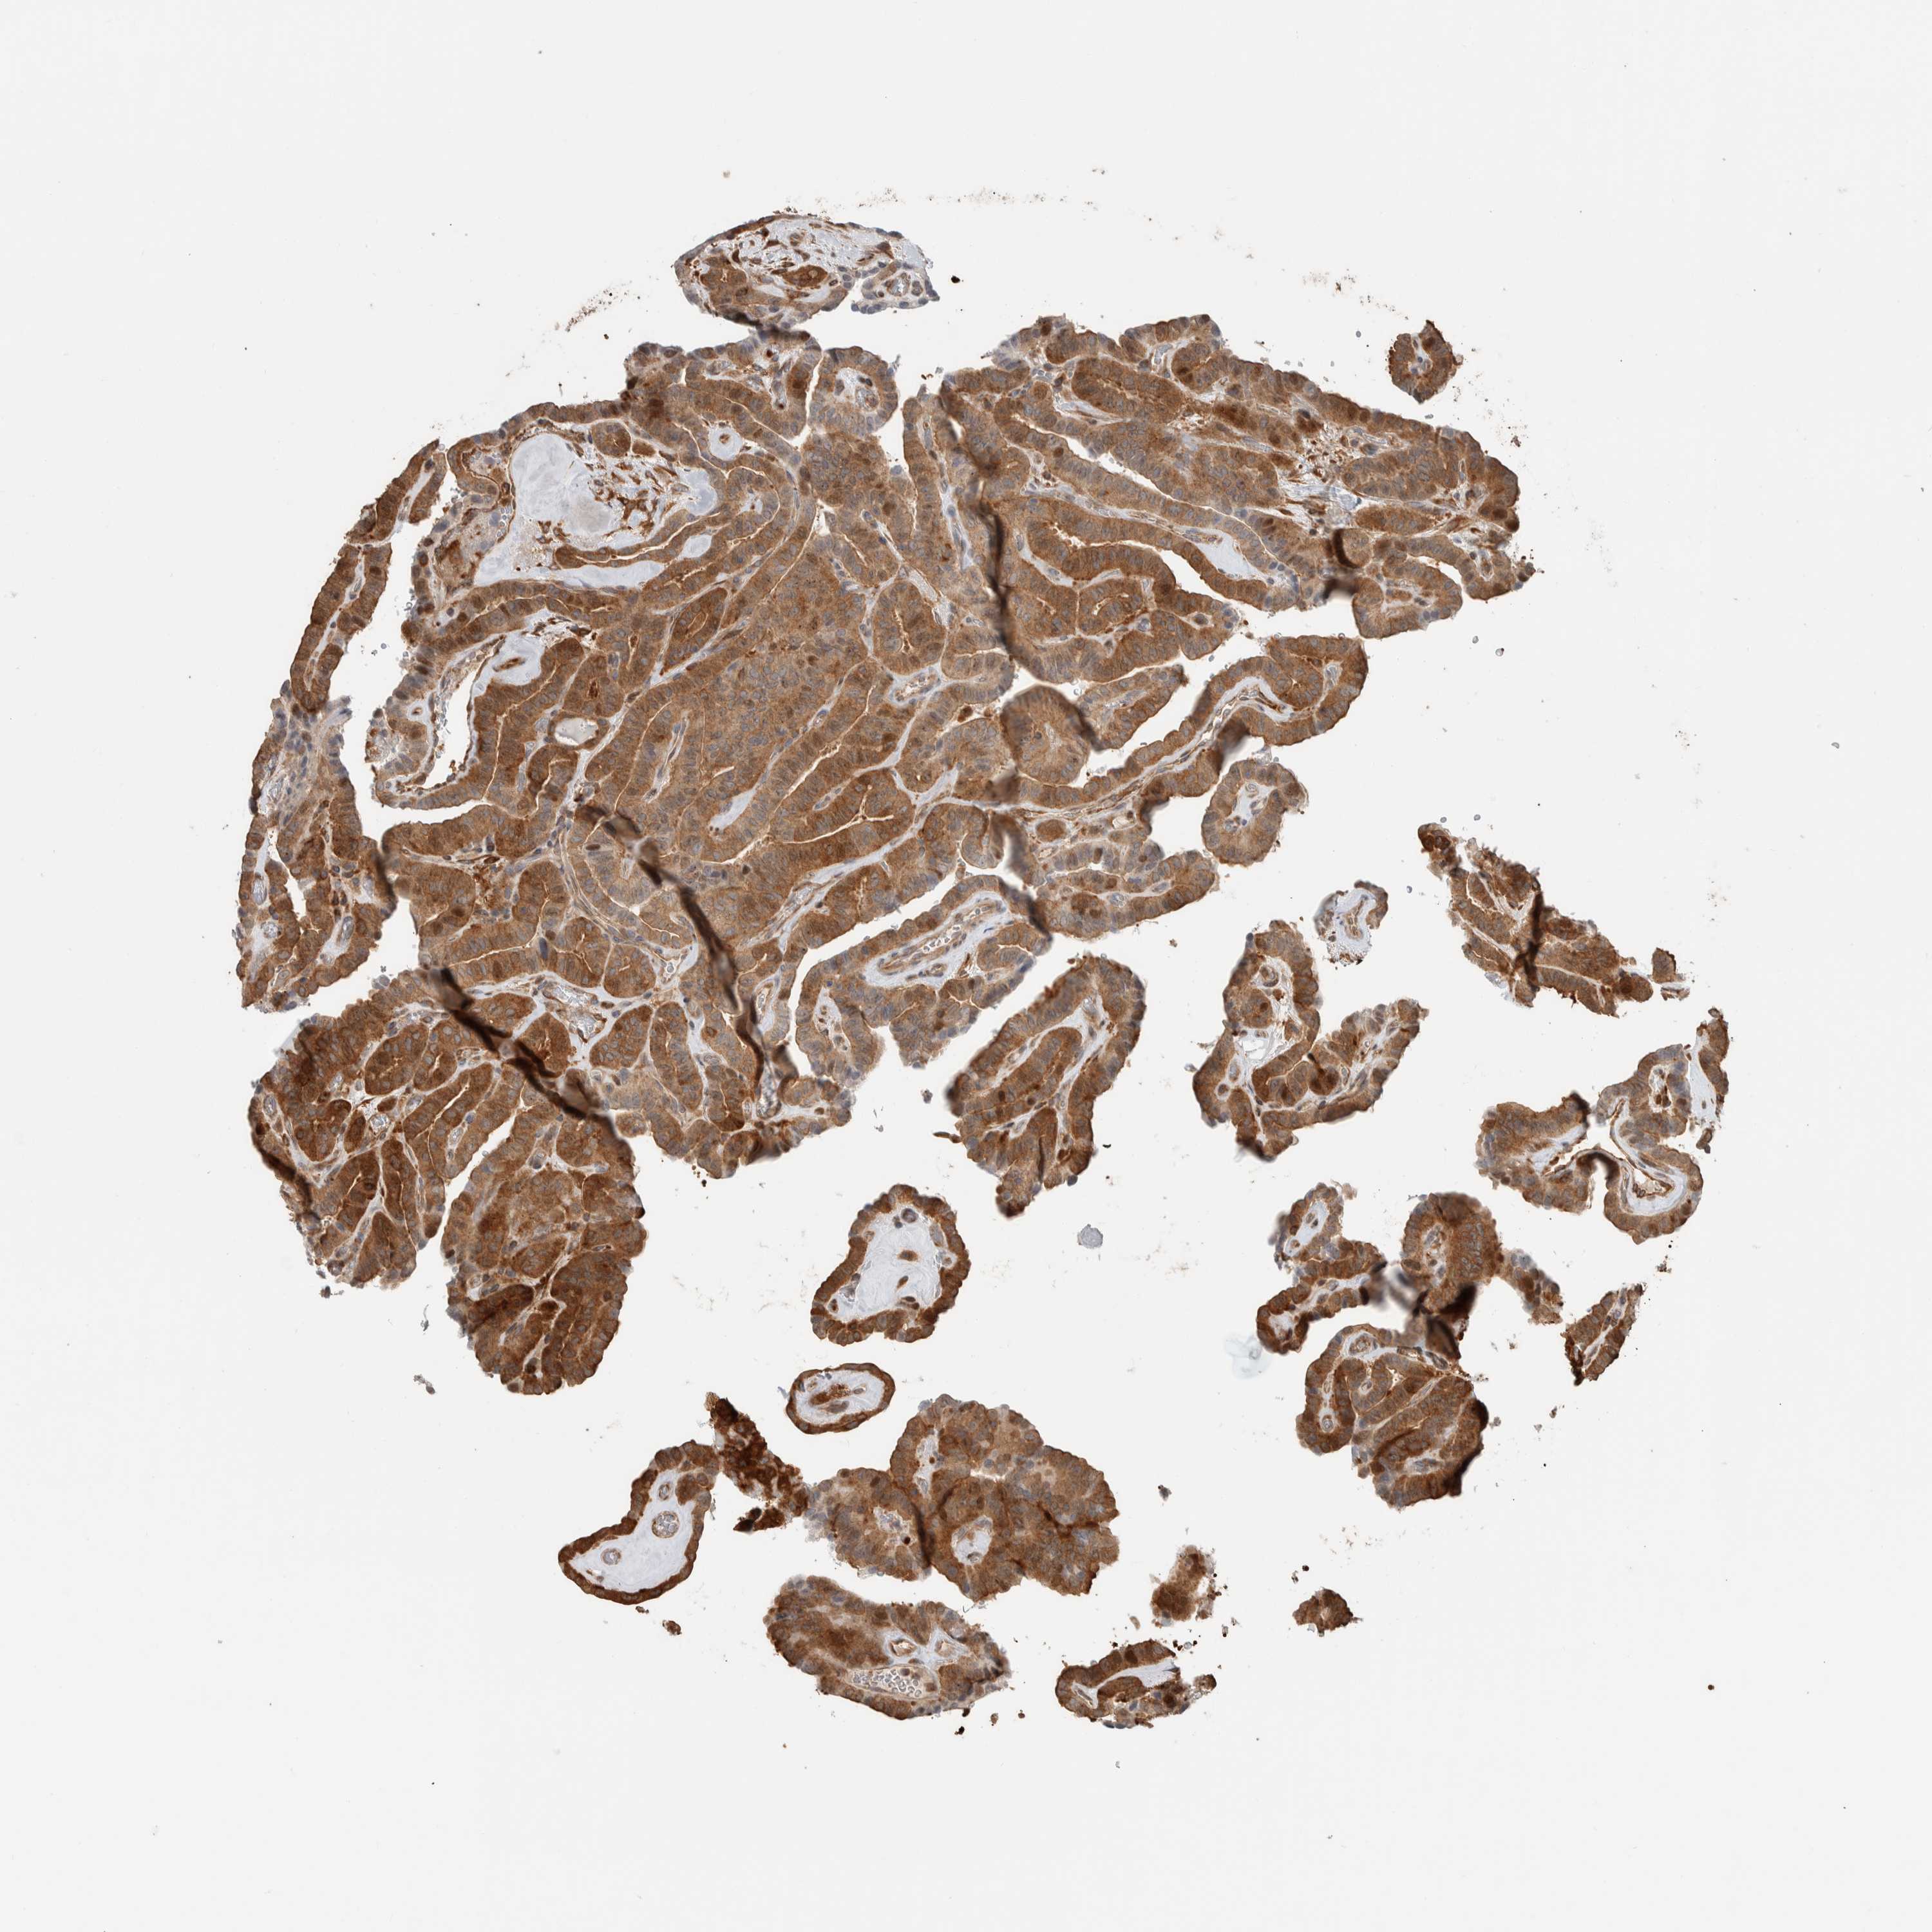

THYROID CANCER - Protein expressioni

A mouse-over function shows sample information and annotation data. Click on an image to view it in a full screen mode. Samples can be filtered based on level of antibody staining by selecting one or several of the following categories: high, medium, low and not detected. The assay and annotation is described here.

Note that samples used for immunohistochemistry by the Human Protein Atlas do not correspond to samples in the TCGA dataset.

Antibody stainingi

Antibody staining in the annotated cell types in the current human tissue is reported as not detected, low, medium, or high, based on conventional immunohistochemistry profiling in selected tissues. This score is based on the combination of the staining intensity and fraction of stained cells.

Each image is clickable and will lead to virtual microscopy that enables deeper exploration of all samples and also displays staining intensity scores, fraction scores and subcellular localization as well as patient and tissue information for each sample.

Antibody HPA023319

Antibody HPA023320

Antibody HPA023321

Antibody HPA023325

Staining

High

Medium

Low

Not detected

Intensity

Strong

Moderate

Weak

Negative

Quantity

>75%

75%-25%

<25%

None

Location

Nuclear

Cytoplasmic/membranous

Cytoplasmic/membranous,nuclear

Papillary adenocarcinoma, NOS

Follicular adenoma carcinoma, NOS